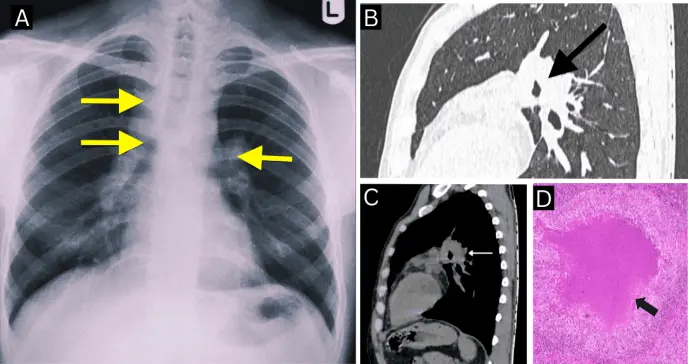

Una radiografía de tórax reveló prominencia hiliar bilateral y ensanchamiento del paratraqueal derecho. Con estos hallazgos, se procedió a realizar una tomografía computarizada (TC) de tórax, que evidenció adenopatías paratraqueales y subcarinales del lado derecho, con una configuración que llamó la atención del equipo médico: los ganglios linfáticos mostraban hipodensidad central con realce periférico, dispuestos de forma anular alrededor de la vía aérea. Este patrón, conocido como el signo de "Medu Vada", fue claramente identificado en la ventana mediastínica.

No se observaron lesiones cavitarias ni compromiso parenquimatoso pulmonar activo. Estos hallazgos orientaron el diagnóstico hacia una linfadenopatía mediastínica con necrosis central.

Los autores (Sivagnaname et al) destacan que este caso resalta el valor diagnóstico del signo de "Medu Vada", una configuración radiológica anular provocada por ganglios linfáticos agrandados que circunscriben la vía aérea central.

En las tomografías, los ganglios afectados por tuberculosis pueden adoptar esta morfología, producto de la necrosis central con realce periférico y la disposición anatómica que recuerda a la forma del popular alimento del sur asiático.

A diferencia de la clásica "rosquilla", el Medu Vada tiene un contorno más irregular, lo cual lo convierte en una analogía más precisa para describir la imagen de ganglios linfáticos conglomerados y lobulados. Esta referencia cultural también ha demostrado ser útil para facilitar el aprendizaje entre profesionales de la salud, sobre todo en regiones endémicas de tuberculosis.